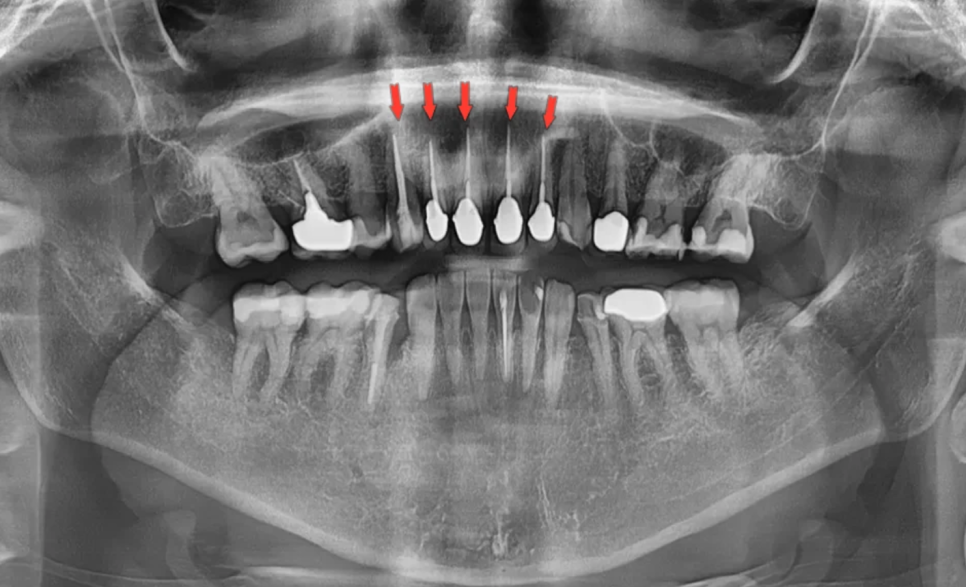

초진 검사 – 파노라마 및 안모 평가

처음 내원하셨을 때 파노라마 엑스레이를 촬영하여 전체적인 상태를 확인했습니다. 촬영 결과, 윗쪽 작은앞니부터 반대편 작은앞니까지(4개 치아) 는 이미 신경치료 후 포스트와 코어가 들어가 있는 상태였습니다. 오른쪽 송곳니는 신경치료 후 코어까지만 진행되어 크라운 없이 그대로 있었고, 왼쪽 송곳니는 레진으로 수복된 상태였습니다.

총 5새의 치아가 신경치료가 되어 있었습니다